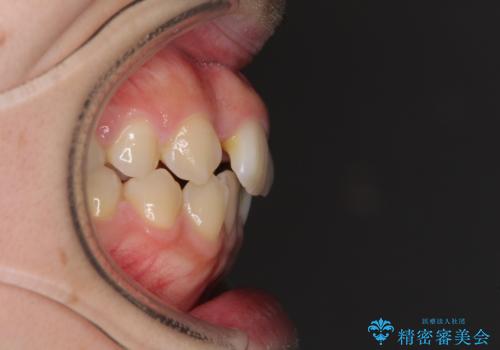

- 右上の八重歯と、左下八重歯を抜いてしまったことを気にして来院された患者様です。

下顎は既に犬歯を1本抜歯しているため、上顎右側第一小臼歯を抜歯し、ワイヤー装置にて歯列を整えることとしました。

変則的な抜歯となるため、正中と人中がずれる可能性がありましたが、仕上がりは上下正中を揃えることができました。